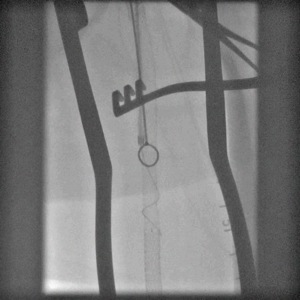

When conduit is limited, or PTFE or cadaver vein is being considered, in the setting of occluded SFA stents, I have found that it is possible and perhaps preferable to attempt removal of these stents using remote endarterectomy.

The CTA, particularly with 3D reconstruction, is helpful in planning these cases.

The additional material needed is fluoroscopy and endovascular skills. Directing a subintimal Glidewire helps free the stent and aid passage of the Moll ring dissector.

Adding cold saline seems to help shrink the stents. A plaque free distal end point allow the stents to be removed with a gentle tug.

I put these patients on coumadin anticoagulation. Surveillance is needed for recurrent stenoses -typically these occur randomly as focal TASC A stenoses, and likely represent remnant medial tissues that have caused intimal hyperplasia. This may be particularly amenable to treatment with drug eluting balloons. Failure as thrombosis typically is limited to the treated vessel without the embolism seen when PTFE grafts fail. Failure tends to occur in smokers. Inability to pass the dissector is usually seen in patients with heavy calcification -diabetics, renal failure, and I would avoid attempting remote endarterectomy in these patients. When the dissectors fail to pass, cutting down and directly endarterectomizing the vessel and resuming remote endarterectomy is feasible. The common femoral artery is repaired with a patch. I try to avoid having to place a distal stent and when a tapered end point, as in a successful carotid endarterectomy, is achieved, usually unnecessary.